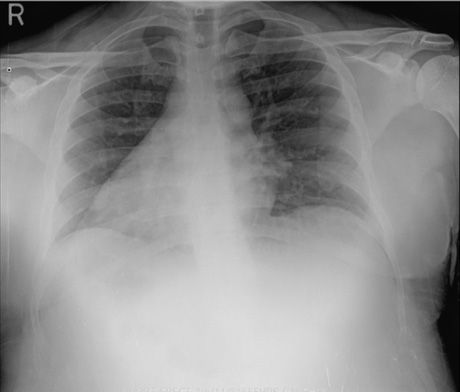

Physical examination revealed right upper quadrant abdominal tenderness, but no pallor, jaundice, or scleral icterus. No cardiac, respiratory, or neurologic abnormalities were found. Chest films and full body CT scans were significant for situs inversus totalis with polysplenia (multiple small spleens1). The chest radiograph, Figure at left, shows the dextrocardia that is characterisitc of situs inversus totalis. Polysplenia is seen (arrows) on the abdominal CT scan, Figure below. A white blood cell (WBC) count with differential revealed a slight leukocytosis (leukocyte count, 13 x 103/µL), but all other values were within normal limits. Following 2 days of supportive treatment, the patient’s temperature spiked, peaking at 41oC (106.1oF) despite interval increase in antipyretics and use of cooling blankets. The WBC count increased to 23 x 103/µL while the patient was receiving empiric antibiotic treatment with vancomycin, ceftriaxone, and metronidazole. Multiple blood cultures; tests for influenza A and B antigens, H1N1 antigen, and Clostridium difficile toxin; stool guaiac test; hepatitis panel; urine culture; and stool cultures for Giardia, Cryptosporidium, and ova and parasites all yielded negative results.